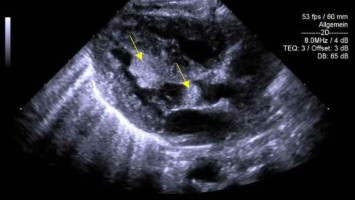

Wie sinnvoll ist ein Präeklampsie-Screening im 3. Trimenon?

Präeklampsien treten mehrheitlich rund um den Geburtstermin auf – therapeutisch bleibt dann meist nur die Einleitung. Doch die Folgen reichen weit über die Entbindung hinaus: Das Risiko für Herzinfarkt, Schlaganfall und Thrombose steigt deutlich. Könnte ein gezieltes Screening im dritten Trimenon die Prognose verbessern?

Präeklampsie einschätzen bevor es kritisch wird

Präeklampsie manifestiert sich bei manchen Schwangeren auf Leber, Niere oder sogar die Lunge. Eine differenzierte Diagnostik hilft, die Schwere und Dynamik der Erkrankung frühzeitig zu erkennen sowie fetale und maternale Komplikationen zu vermeiden. Welche Rolle spielen spezifische angiogene Marker? Und wann ist schnelles Handeln gefragt?

Digitales Blutdruckmessgerät/© Kotchakorn / Stock.adobe.com (Symbolbild mit Fotomodell), Injektionsnadeln für Regionalanästhesie/© zlikovec / Getty Images / iStock, Reanimation/© Rea / stock.adobe.com, Langzeit-EKG mit junktionalem Ersatzrhythmus/© O. Schäfer, Fokussierter Herzultraschall (FoCUS)/© Dieter von Ow / all rights reserved Springer Medizin Verlag GmbH, Pulsoximeter wird an Finger angeschlossen/© Yakobchuk Olena / stock.adobe.com, Rhabdomyom im Kindesalter /© Höck M et al. doi.org/10.1007/s00112-025-02259-w unter CC-BY 4.0, Eine Pinzette wird vom Tisch genommen während einer OP/© JazzIRT / Getty Images / iStock (Symbolbild mit Fotomodellen), Venöse CT-Angiografie: Sinusthrombose/© Wohlfahrt L. et al. / all rights reserved Springer Medizin Verlag GmbH, Übergabesituation im Herzkatheterlabor/© Ernst M et al. / all rights reserved Springer Medizin Verlag GmbH (Symbolbild mit Fotomodellen), Frau misst Blutdruck/© Microgen / stock.adobe.com (Symbolbild mit Fotomodell), Transösophageale Echokardiographie (fTEE), 4‑Kammer-Blick/© Michels M et al. / all rights reserved Springer Medizin Verlag GmbH, Screening auf Präeklampsie/© Musik T et al. / all rights reserved Springer Medizin Verlag GmbH, Arzt nimmt Schwangeren Blut ab/© Andrey Popov / stock.adobe.com (Symbolbild mit Fotomodellen), Patient im Gespräch mit Ärztin/© sebra / stock.adobe.com (Symbolbild mit Fotomodellen), Mann hält Tablette und ein Glas Wasser in den Händen/© somenski / Fotolia (Symbolbild mit Fotomodell), Herpes Zoster am Rücken/© Mumemories / Getty Images / iStock (Symbolbild mit Fotomodell), EKG befunden mit System - EKG Essential/© Springer Medizin Verlag GmbH